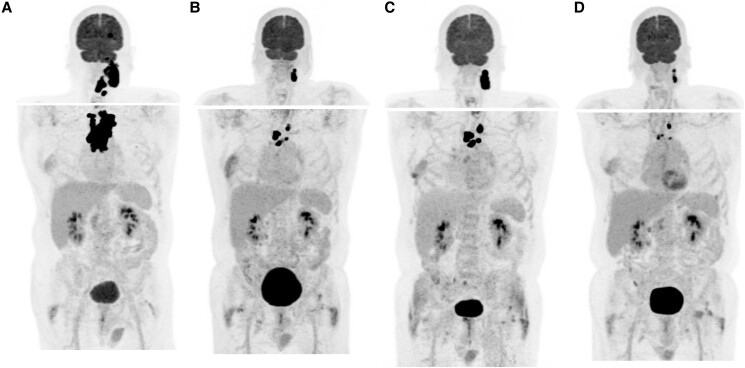

A 65-year-old patient presented with recurrent, locally advanced poorly differentiated thyroid cancer despite 2 neck surgeries, and with newly diagnosed brain and skull base metastases. He was treated with palliative stereotactic radiosurgery to the brain and skull base lesions. Thereafter, as no targetable genetic alteration was identified and antiangiogenic multikinase inhibitors were deemed at high risk of hemorrhagic complications, off-label systemic therapies were considered. The mechanistic target of rapamycin (mTOR) inhibitor everolimus could not be obtained due to lack of insurance coverage, so the patient was treated with single-agent pembrolizumab. He showed an initial remarkable response, but unfortunately had disease progression in the neck and upper mediastinum after 1 year of therapy. At that time, he was treated with external beam radiotherapy, with concomitant pembrolizumab. He was then found to have an CTSB::ALK fusion, which has previously been described in 2 cases of thyroid cancer. However, as he showed a positive response to radiation with pembrolizumab, he continued single-agent immune checkpoint inhibition and had a persistent marked response almost a year after completing radiation. The patient was then followed at an outside institution and was transitioned to hospice at time of progression per his preference. He died 4 years after his initial diagnosis.

Abstract Image